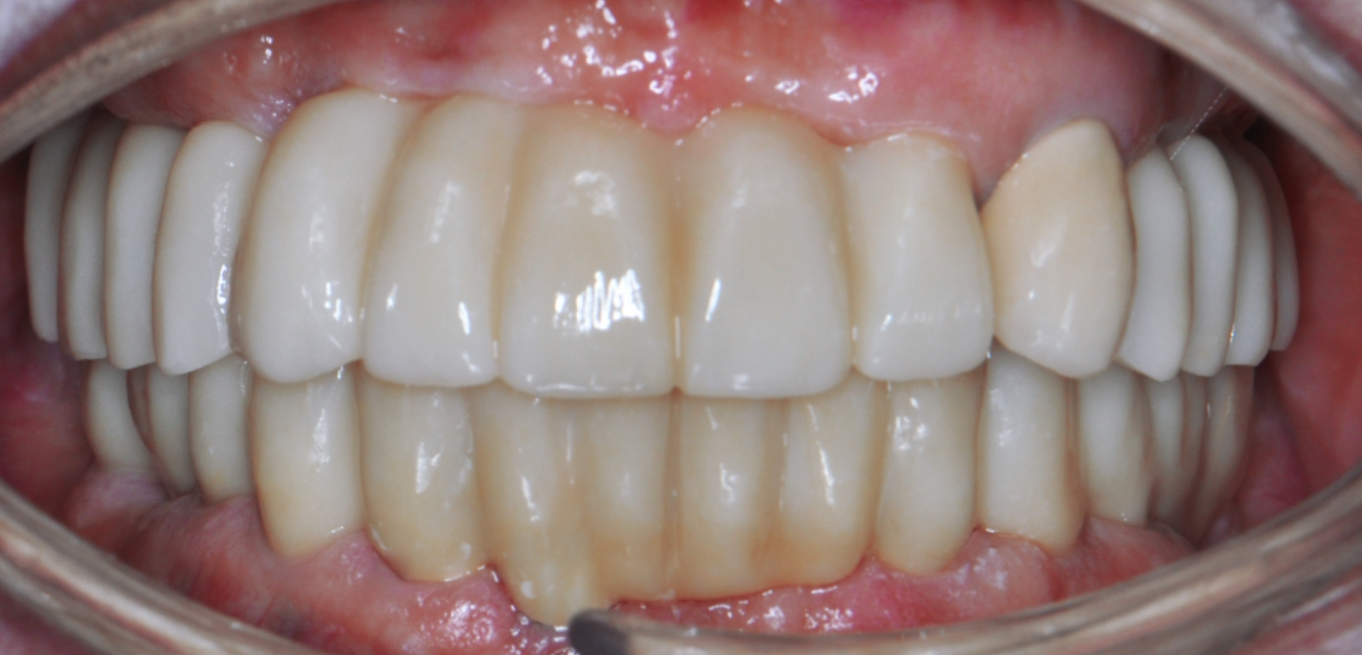

Before & After

Drag Before After

버튼을 움직여서 변화를 확인해보세요.